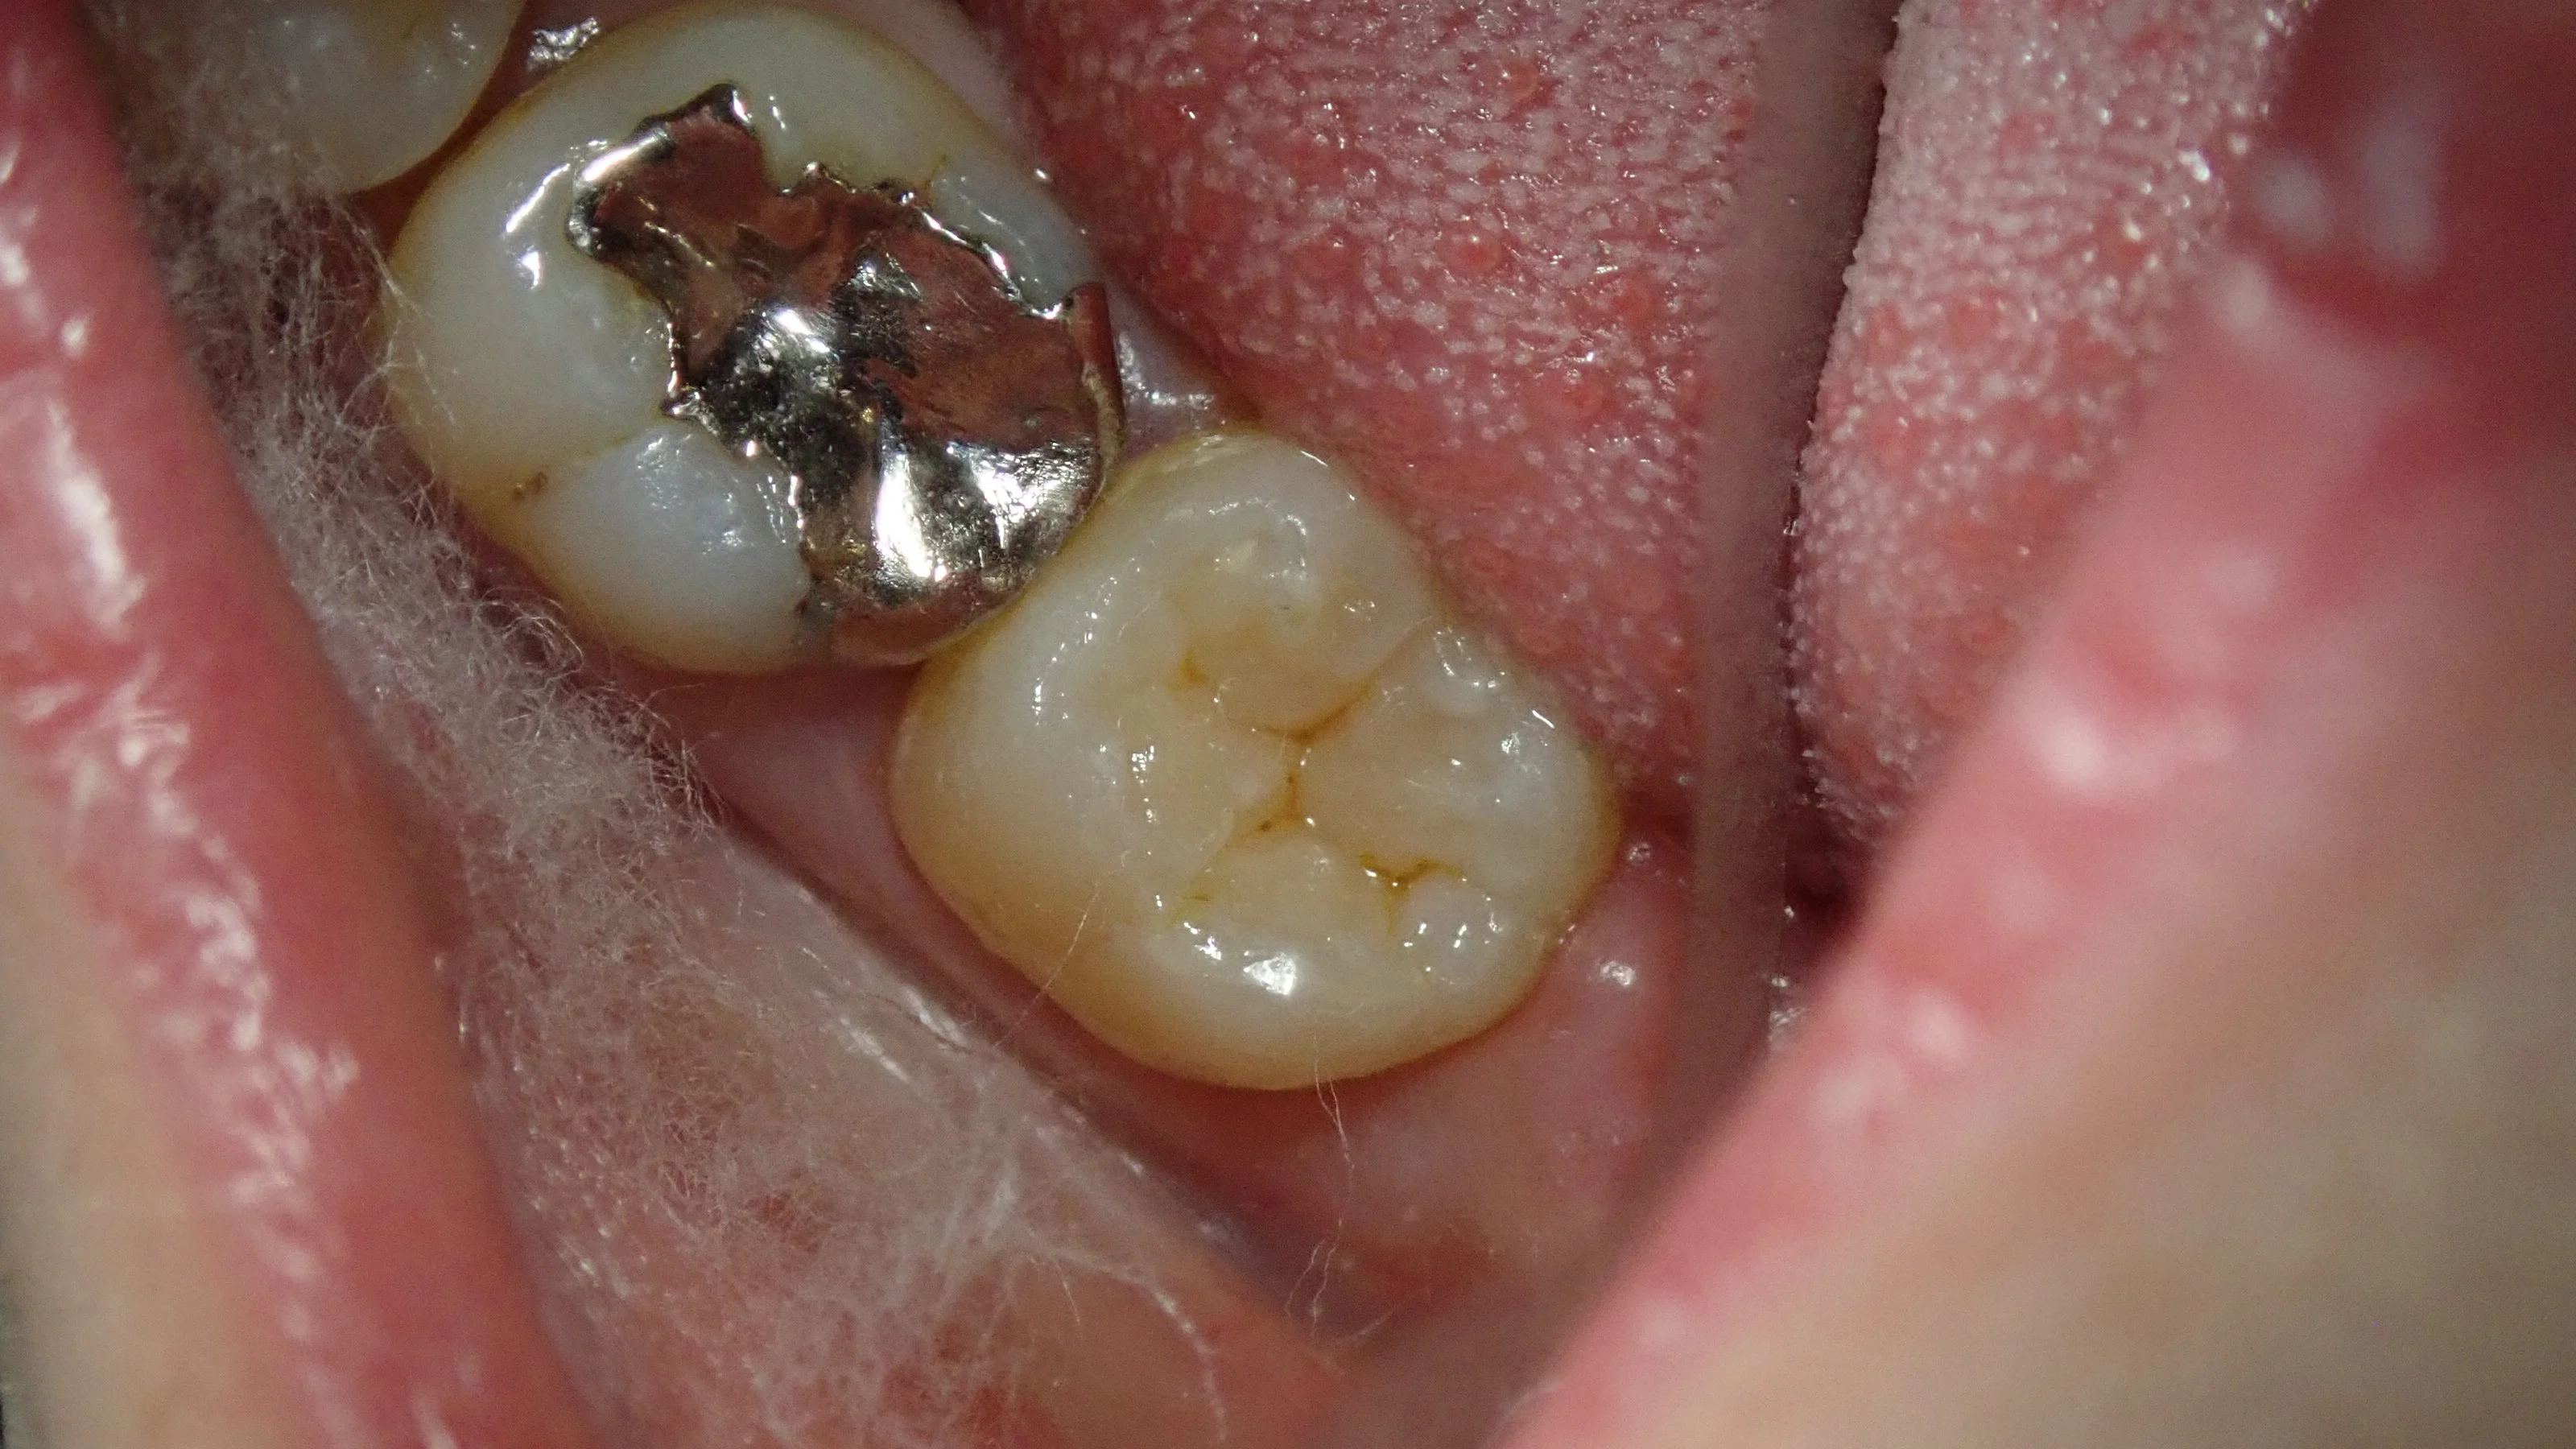

詰めた後。

奥2本のダイレクトボンディング|坂寄歯科医院(取手市藤代) - 画像3

って感じになっちゃいました・・・。